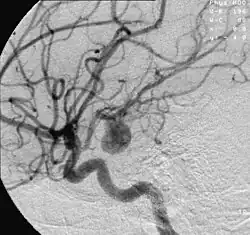

Embolização de Aneurisma Cerebral. Acima: pré-operatório. Abaixo: após colocação de molas destacáveis de Guglielmi e stent diversor de fluxo

O exame padrão ouro para detecção de aneurisma cerebral não é a tomografia ou a ressonância magnética, e sim o cateterismo cerebral de 4 vasos, denominado angiografia cerebral. Entretanto, não costuma ser o primeiro exame realizado.

O tratamento por embolização dos aneurismas cerebrais começa com a inserção de um cateter (pequeno tubo plástico) na raiz da coxa, na artéria femoral na perna do paciente e navegação dele pelos vasos arteriais, passando pela pelva, abdômen, tórax, pescoço e base do crânio até o aneurisma. Através desta viagem pelo corpo, retificadas pelo cateter, pequenas molas ou espirais de platina são inseridas aos poucos dentro do aneurisma. O processo é assistido por meio de imagens radiológicas, visualizadas em um monitor de vídeo. Ao serem destacadas do cateter são desdobradas dentro da luz no aneurisma, ocupando aos poucos o interior, interferindo no fluxo de sangue para o interior do aneurisma, causando coagulação da luz, redução da pressão interna provocada pela pressão sanguínea e prevenindo sua ruptura. As molas são feitas de platina para que eles possam ser visíveis pelo raio x e bastante flexíveis para conformar-se com a forma de aneurisma e tentar evitar que ele se rompa. Um grande número de pacientes no mundo inteiro já foram tratados com molas de platina destacáveis. As micro-molas mais utilizadas para a embolização do aneurisma são as molas destacáveis de Guglielmi.

Os médicos, preferencialmente neurorradiologistas experientes em intervenções por angiografia encefálica, usam a tecnologia de raios-X em tempo real, chamada visualização fluoroscópica (radioscopia), para visualizar o interior dos vasos sanguíneos. As características externas do aneurisma apenas podem ser visibilizadas pela cirurgia aberta.